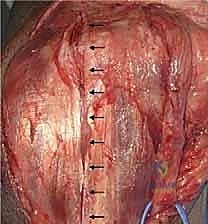

2. الشق الجراحي وحماية الأعصاب

يقوم الدكتور هطيف بعمل شق طولي خلف الكوع. الخطوة الأكثر أهمية هنا هي تحديد العصب الزندي (Ulnar Nerve) وعزله وحمايته بعناية فائقة باستخدام تقنيات الجراحة الميكروسكوبية الدقيقة لتجنب أي تلف قد يؤدي إلى ضعف في اليد.